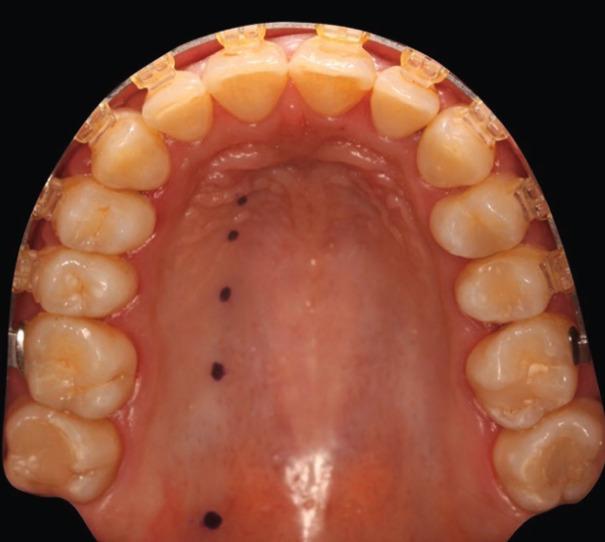

A pilot case series study was performed in a private clinic during February 2020. The scans were performed with a Mindray® M9 ultrasound machine (Mindray North America, NJ, USA) coupled to an L16-4Hs® hockey-type angled probe. For each participant, the arterial path and thickness of the palatal fibromucosa were determined at 5 different points.

2020年2月在一家私人诊所进行了一项初步病例系列研究。扫描使用迈瑞®M9超声诊断仪(迈瑞北美公司,美国新泽西州),配备L16 - 4Hs®曲棍球型角度探头。对于每位参与者,在5个不同点确定腭动脉路径和腭纤维黏膜的厚度。